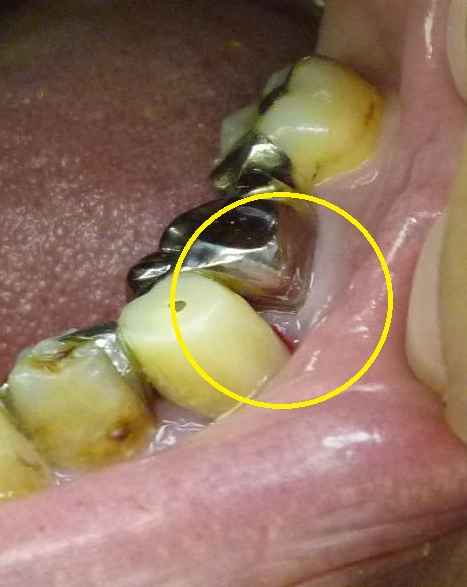

通い始めた左下。 治療が終わりましたが、改善しません。 おそらく黄色い丸の中央付近に、小さな穴が空いている、と思われます。